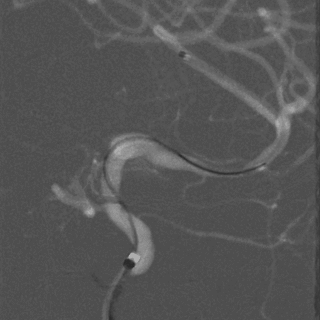

术后图像显示支架打开及贴壁良好。

术后工作位造影

术后侧位造影

术后正位造影